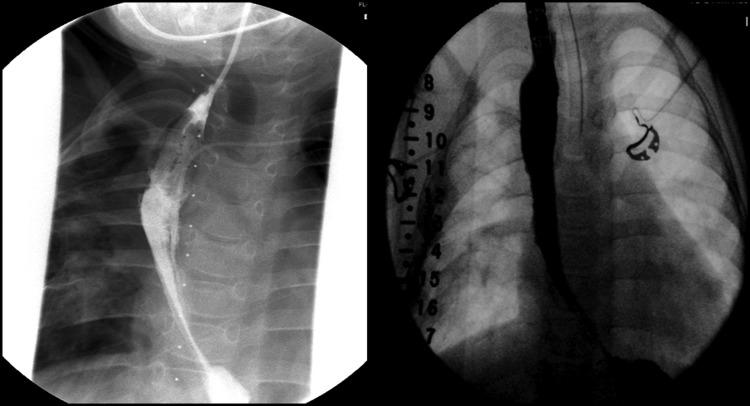

The Foker process is a method of esophageal lengthening through axial tension-induced growth, allowing for subsequent primary reconstruction of the esophagus in esophageal atresia (EA). In this unique case, the Foker process was used to grow the remaining esophageal segment long enough to attain esophageal continuity following failed colonic interpositions for long-gap esophageal atresia (LGEA). Initially developed for the treatment of LGEA in neonates, this case demonstrates that (i) an active esophageal lengthening response may still be present beyond the neonate time-period; and, (ii) the Foker process can be used to restore esophageal continuity following a failed colonic interposition if the lower esophageal segment is still present.

福克手术是一种通过轴向张力诱导生长来延长食管的方法,可用于食管闭锁(EA)患者后续的食管一期重建。在这个独特的病例中,对于长段食管闭锁(LGEA)患者,在结肠代食管术失败后,采用福克手术将剩余食管段延长至足够长度以实现食管连续性。该手术最初是为治疗新生儿LGEA而开发的,此病例表明:(i)在新生儿期之后可能仍存在活跃的食管延长反应;(ii)如果食管下段仍然存在,福克手术可用于在结肠代食管术失败后恢复食管连续性。